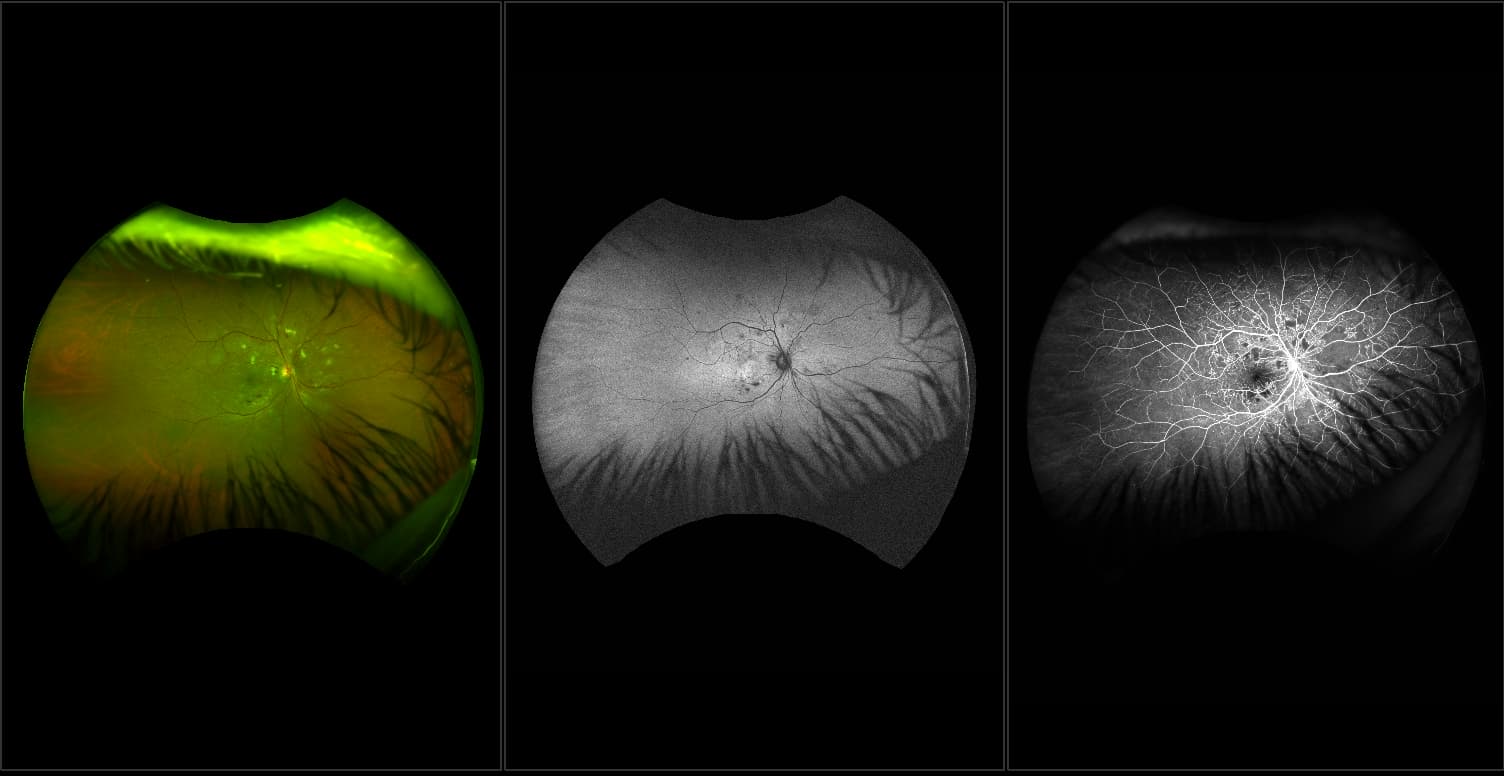

California - Large Pars Plana Cysts - Steered, RG

Pars plana cysts are a common peripheral retinal pathology that do not raise much clinical concern. They do not affect the central vision and observation alone is typically recommended. Pars plana cysts are something to be considered when peripheral retinal elevation is noted on routine exam.